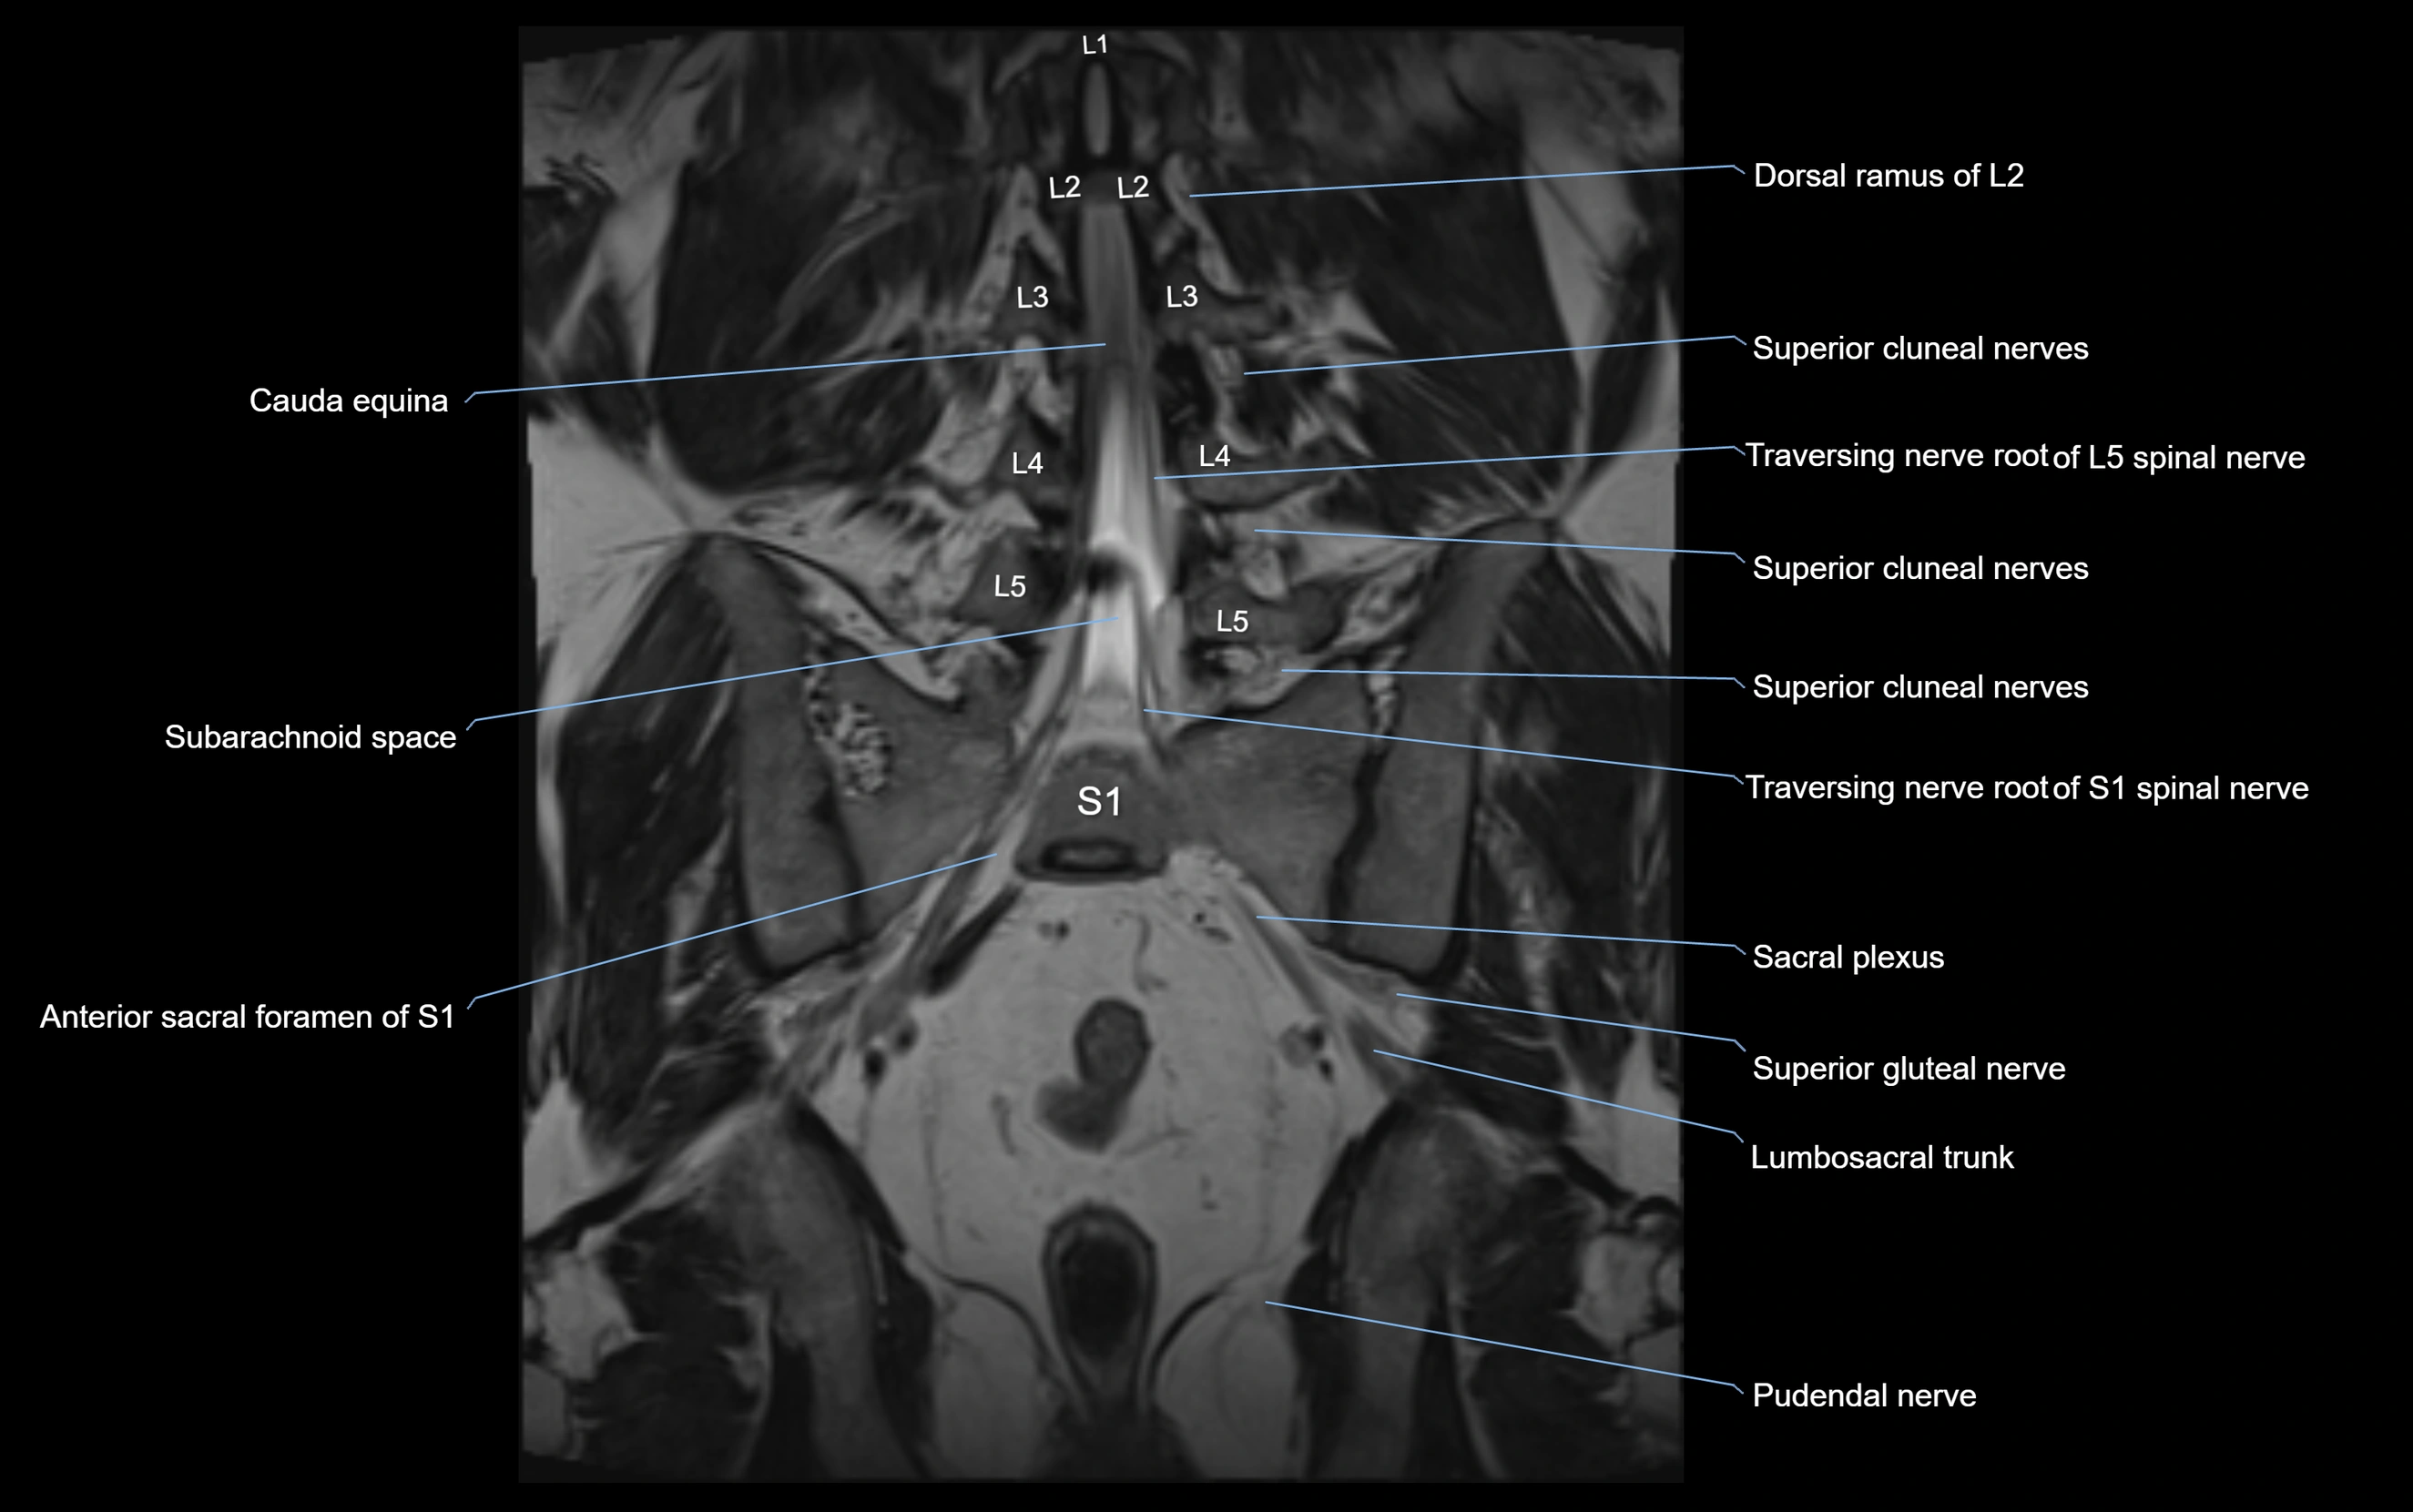

MRI Appearance

T1-weighted images:

• Nerve appears as a very thin low-to-intermediate signal intensity structure

• Surrounded by bright fat, aiding visualization

T2-weighted images:

• Nerve shows intermediate to mildly hyperintense signal compared to muscle

• Pathological involvement appears brighter

STIR (Short Tau Inversion Recovery):

• Normal nerve appears dark

• Inflamed or entrapped nerve appears bright hyperintense

T1 Fat-Sat Post-Contrast:

• Normal nerve enhances minimally

• Pathologic nerve (neuritis, entrapment, tumor infiltration) shows focal or diffuse enhancement

3D T2 SPACE / CISS:

• Nerve appears intermediate to mildly hyperintense compared to muscle

• Surrounded by bright fat or CSF, improving visualization

• Best sequence for mapping small pelvic nerves such as the anococcygeal